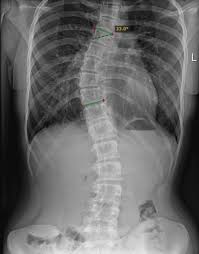

زاوية كوب هي المقياس الطبي الأساسي المستخدم لتحديد شدة اعوجاج العمود الفقري. يقوم الطبيب بقياسها باستخدام الأشعة السينية لتحديد مقدار الانحناء الجانبي للعمود الفقري بالدرجات.

بالتالي، فإن أي تغيّر في زاوية كوب مع العمر يحمل أهمية كبيرة في الخطة العلاجية.

إذا تجاوزت زاوية كوب 30–40 درجة